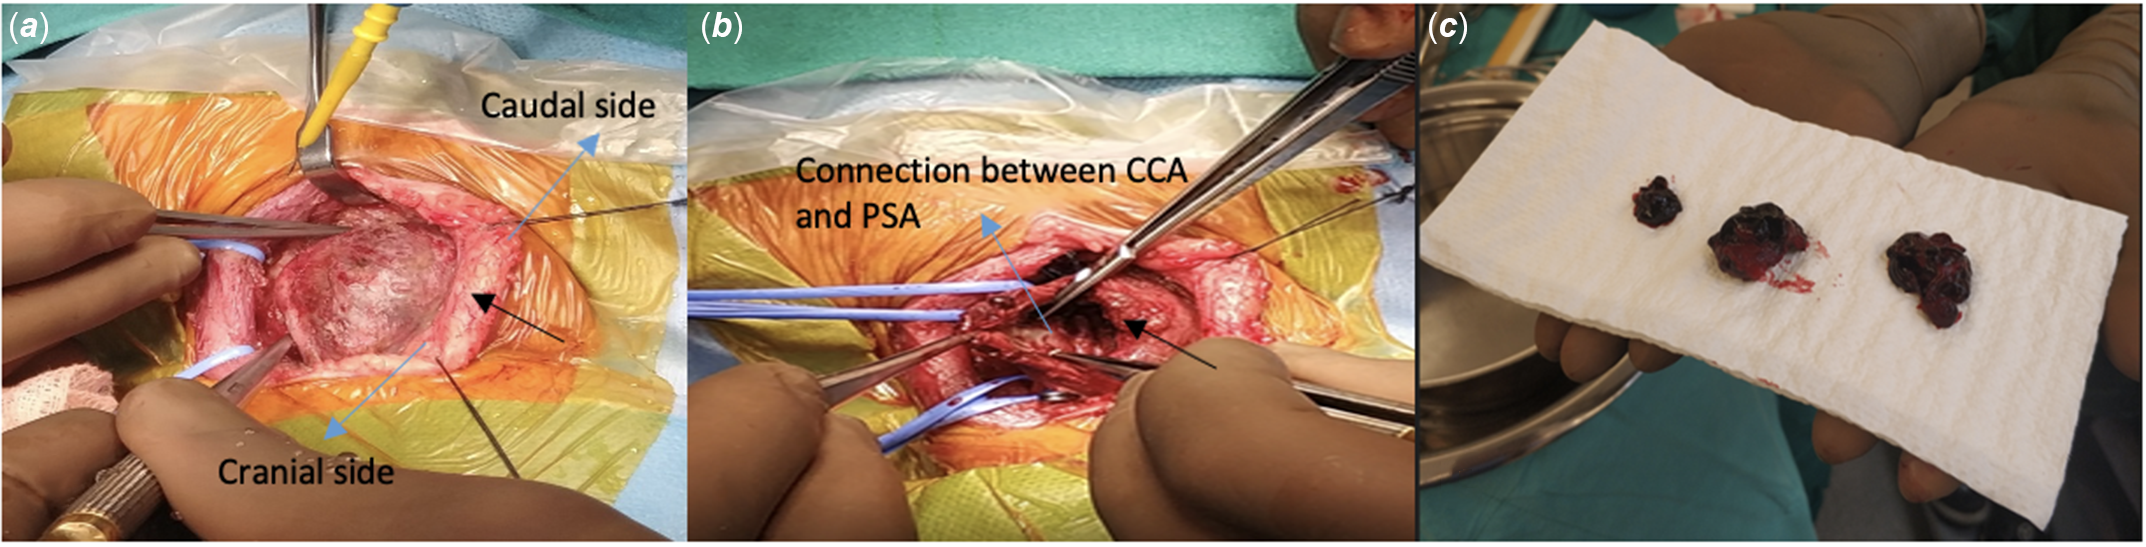

A 6-month-old girl was admitted to the hospital for evaluation for coarctation balloon angioplasty. In medical history, the patient was operated on due to aortopulmonary window, interrupted aortic arch, and aortic coarctation when she was 12 days old. Balloon angioplasty was performed for recoarctation 1 month later. Then, she underwent a second operation due to left phrenic nerve palsy. The patient was referred for evaluation due to recoarctation. On physical examination, she weighed 4.3 kg and revealed scars from previous surgeries around the left thoracotomy and left subcostal region. The femoral pulses were weak. A 2/6 systolic ejection murmur was heard in the interscapular region. On the echocardiogram, there were left ventricular hypertrophy and diastolic flow pattern in descending aorta. It was decided to perform a balloon coarctation angioplasty for the recurrence of the aortic coarctation. In the catheter laboratory, efforts to find access from femoral and axillary arteries were unsuccessful. Left common carotid artery access was performed by using an 18-gauge needle and 0.035-inch wire under ultrasound guidance, and a 4F sheath was inserted. Intravenous heparin 30 unit per kilogram was admitted. There were no complications during the procedure (Fig 1). The patient was discharged from the hospital one day after the procedure. After 10 days, the family noticed a prominent mass on the left side of the patient’s neck. The patient was called in for control. During the patient’s examination, a 2 × 2 cm pulsating mass on the left side of the neck, with no signs of infection on the skin, was noted (Fig 2). On ultrasound, a 2 × 2 cm pseudoaneurysm was detected adjacent to the left common carotid artery (Fig 3). To better assess the location. of the pseudoaneurysm, a CT angiography was performed. CT revealed a 3 × 3 cm pseudoaneurysm with a 3 mm connection with the left common carotid artery, located 2 cm below the bifurcation. Due to the pseudoaneurysm, the trachea and surrounding structures were noted to be shifted to the right side (Fig 4). The management was discussed with the department of interventional radiology. A stent graft was not suitable since the patient was an infant. Even the pseudoaneurysm neck was narrow, percutaneous thrombin injection still had a risk of distal emboli, and it was not possible to insert a filter into common carotid artery due to unattainable femoral access. With the department of cardiovascular surgery, it was decided upon to move forward with a surgical treatment plan. During the operation, considering the pseudoaneurysm sac’s growth direction, an incision was made lateral to the right sternocleidomastoid muscle. Sternocleidomastoid was excluded laterally, and the sac was partially exposed with a meticulous dissection. Proximal and distal parts of the carotid artery were identified and clamped after heparinisation. The pseudoaneurysm sac was excised, and the coagulum was removed. 1–2 mm needle hole on carotid artery was localised and closed with separated stitches (Fig 5). The clamps were removed, and the blood flow was re-established. The patient was extubated in the operating room and transferred to the paediatric ICU without any complications. The repeat ultrasound on the post-operative fourth day was normal, and the patient was discharged without any neurologic problems.

Figure 5. (A) Large pseudoaneurysm is seen (Black arrow). (B) The appearance of the pseudoaneurysm after evacuation and its connection with the common carotid artery is seen (Blue arrow). (C) Hematoma draining through the pseudoaneurysm. (CCA: Common carotid artery, PSA: Pseudoaneurysm).